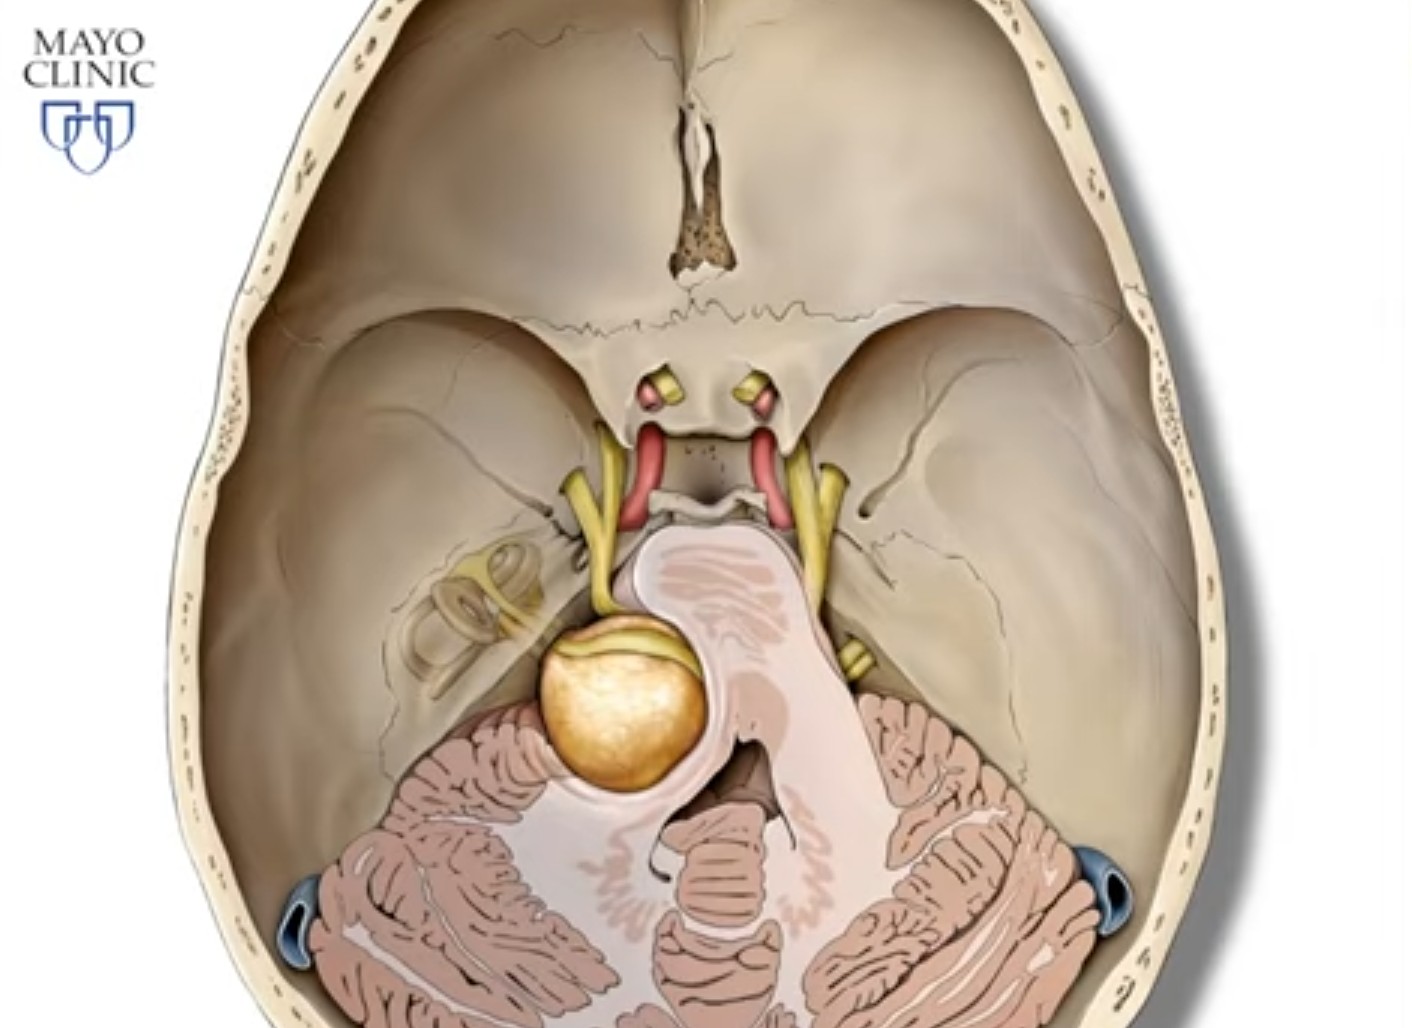

Вблизи преддверно-улиткового нерва проходят: ствол лицевого нерва (VII), тройничный нерв (V), отводящий (IV), языкоглоточный (IX) и блуждающий (X) нервы . По мере роста невриномы в клинической картине могут возникать симптомы сдавления этих нервов, а также прилежащих структур ствола мозга.

Патогенетически выделяют 3 стадии развития вестибулярной шванномы. В первой небольшие размеры образования (до 2,5 см) приводят к нарушению слуха (тугоухости) и вестибулярным расстройствам. Во второй новообразование вырастает до размеров грецкого ореха, оказывает давление на ствол мозга, что приводит к появлению нистагма, дискоординации движений и расстройства равновесия.

В третьей стадии, когда невринома достигает размеров куриного яйца, она вызывает резкое сдавление церебральных структур, гидроцефалию, нарушения зрения и глотания. На этой стадии в тканях головного мозга происходят необратимые изменения, опухоль иноперабельна и является причиной летального исхода.